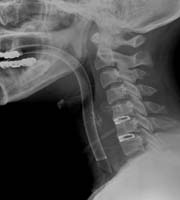

<¸ñµð½ºÅ©>

<¼ö¼úÀü>

<¼ö¼úÈÄ>

¾çÃø

»óÁö ÅëÁõÀ» ÁÖ¼Ò·Î ³»¿øÇÑ È¯ÀÚÀÇ °æÃߺÎ

MRI¼Ò°ß, ¼ö¼úÈÄ ¼Ò°ß